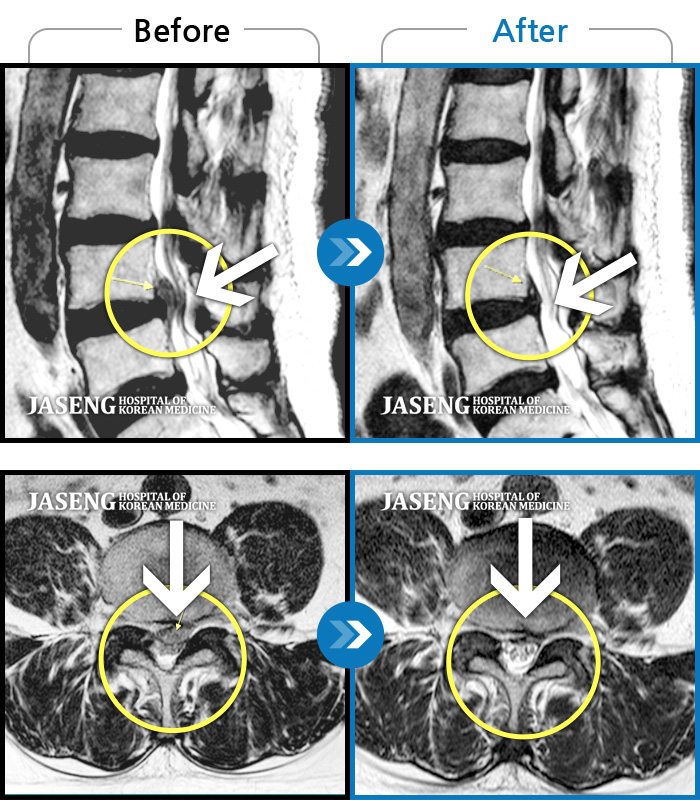

MRI 치료사례

허리통증, 왼쪽 다리 저림 및 근력 저하